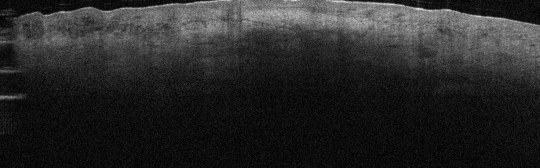

scar1aano

• Loss of normal papillary dermis and reticular dermis contrast

• Single homogenous hyperreflective texture corresponding to densely packed collagen bundles minimal fluid

• Fine vessels may be evident in healing scars

• Can occur with a hyporeflective area underneath scar indicating perivascular lymphocytic infiltrate (*)